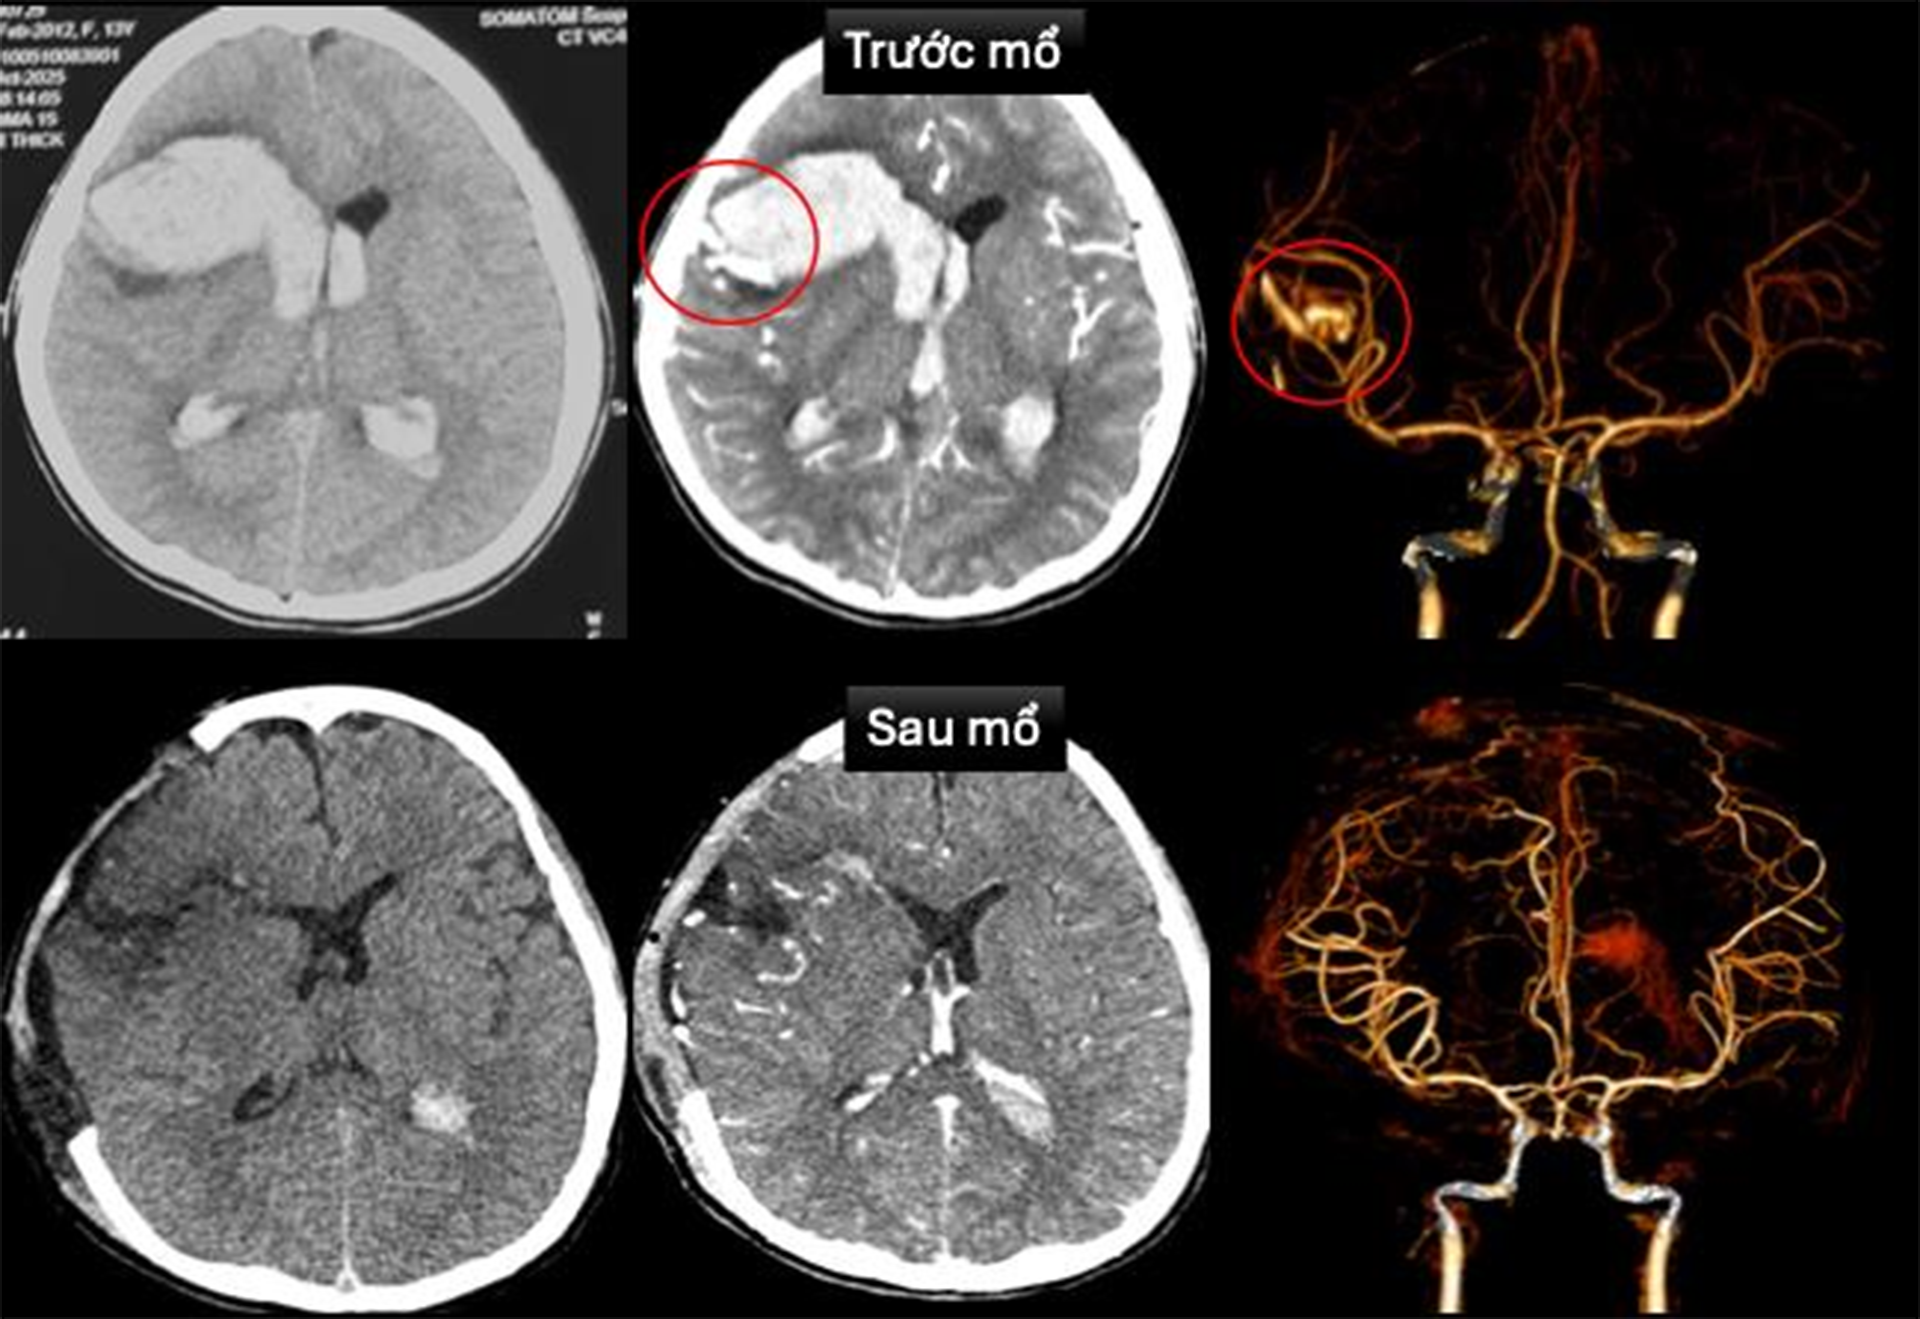

Tại Khoa Cấp cứu, bệnh nhi được ghi nhận hôn mê sâu, thở máy qua nội khí quản, nhịp tim chậm, huyết áp thấp và phải duy trì thuốc vận mạch. Các bác sĩ nhanh chóng tiến hành siêu âm tim, chụp cắt lớp vi tính sọ não dựng hình mạch máu não để chẩn đoán. Kết quả xác định em bị dị dạng động tĩnh mạch trán phải vỡ gây xuất huyết nhu mô não lan vào hệ thống não thất, kèm theo sốc tim, rối loạn nhịp và bệnh cơ tim xốp.

Sau khi hội chẩn đa chuyên khoa, ê-kíp khẩn trương can thiệp cấp cứu. Bác sĩ tim mạch can thiệp đặt máy tạo nhịp tạm thời, đồng thời bác sĩ ngoại thần kinh thực hiện phẫu thuật cấp cứu mở sọ giải áp, vi phẫu cắt dị dạng mạch máu não và lấy máu tụ trong nhu mô não cùng não thất.

Sau mổ, bệnh nhi được chuyển Khoa Hồi sức Ngoại để điều trị hồi sức tích cực, thông khí cơ học, sử dụng thuốc vận mạch và chống phù não. Hiện em T. đã tỉnh táo, chỉ còn yếu nhẹ chân phải. Tình trạng tim mạch ổn định, đã rút được máy tạo nhịp và ngưng thuốc vận mạch. Hình ảnh chụp cắt lớp vi tính sọ não sau mổ không còn ghi nhận dị dạng mạch máu não. Siêu âm tim kiểm tra cho thấy bệnh cơ tim xốp với chức năng co bóp cơ tim cải thiện (EF 65%).